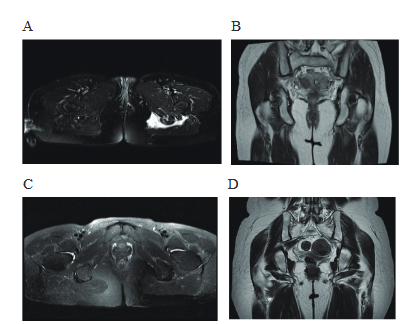

坐骨结节滑囊炎多发于体质瘦弱而久坐工作的中老年人,臀部摩擦、劳损挤压而引起局部炎症,有时被称为“织布臀”或“船夫臀”。以臀部疼痛为主要临床表现,疼痛的性质为牵扯痛,可向一侧下肢放射,严重者可出现行走困难、无法坐位。病因坐骨结节滑囊解剖位置多变,主要位于坐骨结节与臀大肌之间,是为了适合生理及病理的需要,在臀部受压迫及摩擦的基础上生产,不是在胚胎发育中形成的,这些滑囊没有内皮细胞,因此不会产生滑液,但过度摩擦造成滑膜充血、水肿、增厚、渗出,导致滑液增多,压迫周围组织,引起坐骨结节滑囊炎。好发人群:(1)长期坐着工作的瘦弱的老年人或恶病质的病人,例如癌症病人臀部脂肪减少会导致滑囊炎反复发作;(2)在长时间坐着并在工作中处于震动状态,如操纵重型电动缝纫机缝纫女工,拖拉机驾驶员、皮划艇、骑马、轮椅上的截瘫病人、长期卧床病人等;(3)易发生在过度或不适当的体育锻炼时,如长时间坐着、跑步、重复的跳跃及反复踢等。在临床中坐骨结节滑囊炎的病因有反复摩擦、压迫、创伤、感染、结晶沉积等。疼痛机制病变发生在坐骨结节滑囊位于大腿后侧肌群的肌肉与坐骨结节之间,当滑囊反复摩擦及受压时导致滑膜充血、水肿、积液,常常涉及到大腿后侧肌群,诱发肌群的炎症反应,产生疼痛;当囊壁破裂后囊液会沿着臀肌扩散波及坐骨神经及附近的臀下皮神经导致臀部及大腿后侧疼痛。临床表现症状:反复出现的臀部及周围疼痛,可向下肢放射,疼痛的程度轻度不一,坐位平躺时疼痛较明显,身体前倾及拉伸臀部肌肉时(弯腰、跑步、爬楼梯等)疼痛加重,疼痛常影响睡眠。查体:坐骨结节压痛,常可出现“4”试验(+),屈髋屈膝试验(+),直腿抬高试验(-)。辅助检查:ESR,CRP均升高,白细胞正常或轻度升高,其余实验室检查可无异常。MRI检查可以发现坐骨结节周围软组织的炎性病变。MRI提供了骨盆、臀部及周围软组织的全局视图,据此可寻找引起的疼痛病变的具体部位,T2加权像上可明确辨别坐骨结节滑囊炎性病变;此外超声检查也可以作为坐骨结节滑囊炎诊断的良好方式。超声可以显示坐骨结节滑囊炎的位置,在超声图像上可以看到滑囊炎它是一种薄壁的、可压缩的囊性病变。尽管在确认滑囊炎的性质方面有局限性,但它可以帮助区分滑囊炎与该区域的肿瘤。